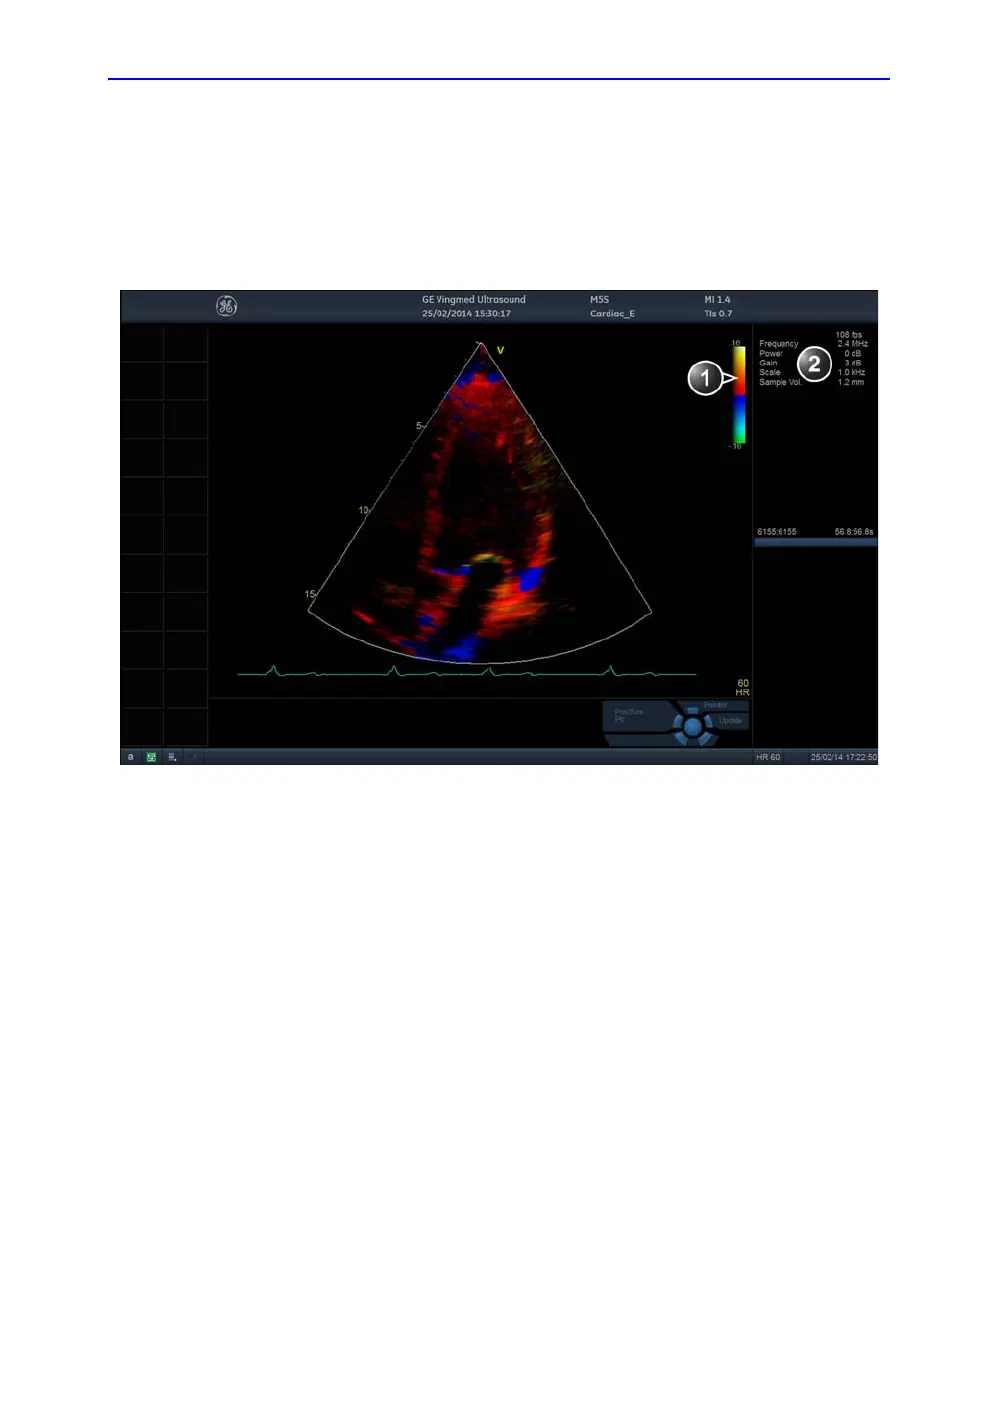

TVI overview

Figure 4-15. The TVI Mode screen

1. TVI color bar

2. Parameter window

Doppler velocity values at discrete points. The information is

stored in a combined format with grayscale imaging during one

or several cardiac cycles with high temporal resolution.